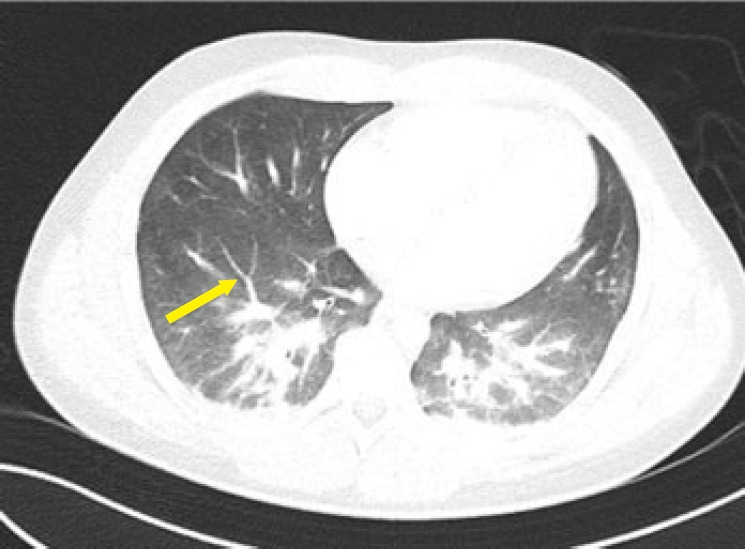

脂肪栓塞综合征(FES)是一种罕见但严重的并发症,最常与创伤有关,特别是长骨骨折。然而,有症状的FES仍然是一个重大的诊断和治疗挑战。我们报告了一个20岁的男子,在摩托车事故中持续多处长骨骨折后,最初表现稳定,经历了快速和致命的FES进展。本病例强调了即使在以前健康的年轻人中,FES的病程也是不可预测的,并强调了早期识别和干预的迫切需要。它还强调了确定可能预测严重后果和死亡率的风险因素的重要性。

Fat embolism syndrome (FES) is a rare but serious complication most commonly associated with trauma, particularly long bone fractures. However, symptomatic FES remains a significant diagnostic and therapeutic challenge. We present the case of a 20-year-old man who, after sustaining multiple long bone fractures in a motorcycle accident and initially appearing stable, experienced a rapid and fatal progression of FES. This case underscores the unpredictable course of FES even in young, previously healthy individuals and highlights the critical need for early recognition and intervention. It also emphasizes the importance of identifying risk factors that may predict severe outcomes and mortality.